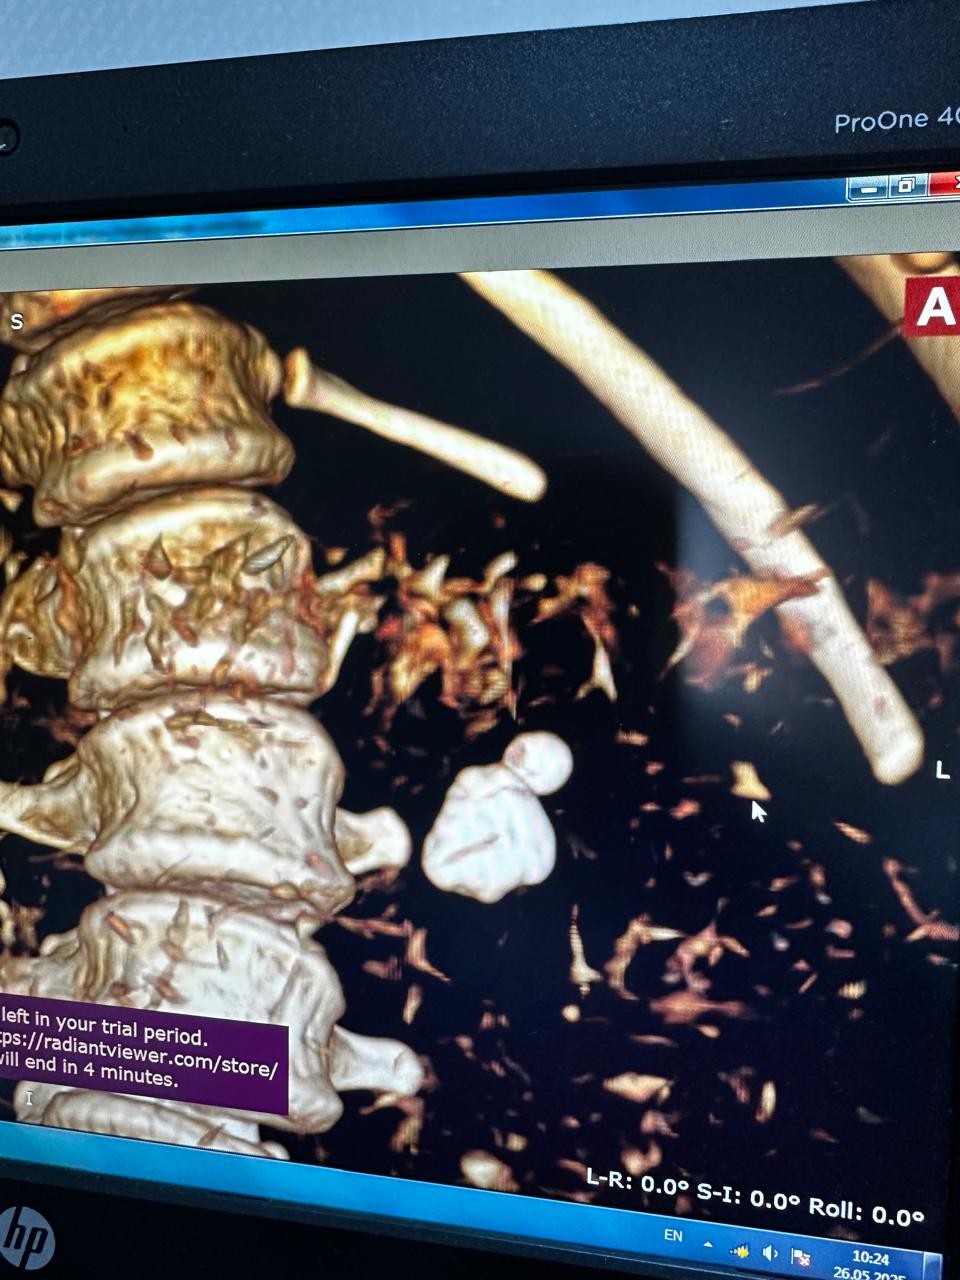

Əməliyyat zamanı xəstənin sol böyrəyindən mərcanvari daş xaric edilib.